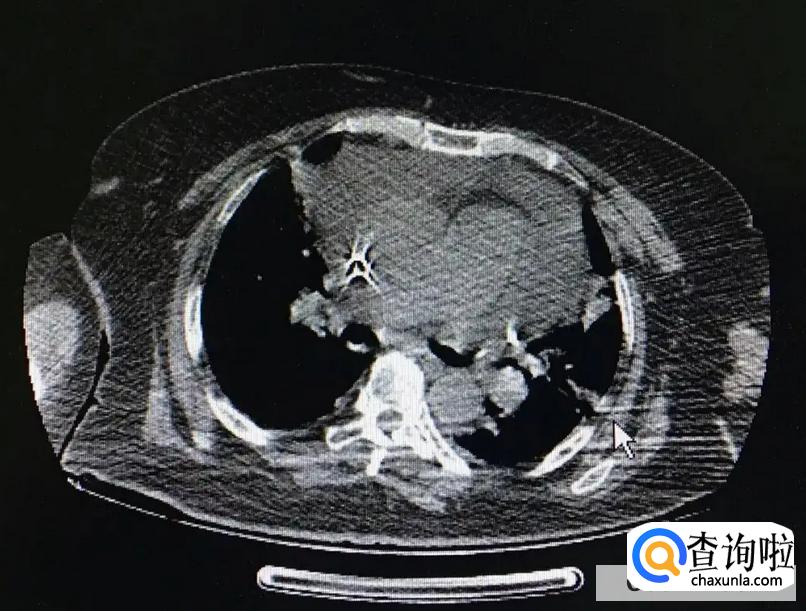

心脏心包积水又被称之为心包积液,它产生的主要症状为急性心包填塞症状。一般表现为循环衰竭。当发生急性的心包填塞时,患者可能会出现心跳过快,脉搏细弱,静脉压升高,动脉压下降。要是情况比较严重的话,很有可能会出现休克的状态,当然还会伴随大汗,心跳快,血压低,甚至,测不出具体的情况。

目前心脏心包积水主要分为急性心包积液和慢性心包积液,其中急性心包积液严重程度取决于积液形成的速度。

一旦出现以后,需要紧急解除心包积液对于心脏的压迫,常见的方式是进行心包穿刺,将积液引出。

而慢性心包积液形成的积液速度是比较缓慢的,因为心脏适应缓慢增加的积液,而心脏症状可能并不是特别的明显。但是长期慢性形成的心包积液可能会使后期回心血量减少,外周淤血情况加重。当然也有一些患者会出现外周浮肿,尤其是下肢。要是患者到了晚期心包积液,可能会有淤血性肝硬化,同时会长期低血压,也会产生众多的危害。